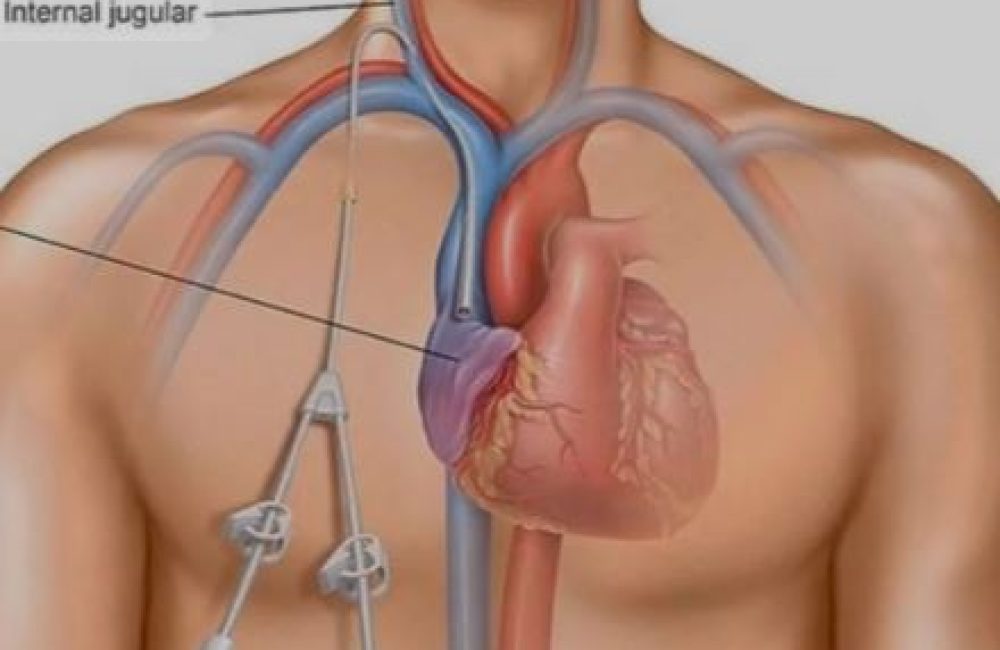

A permacath is typically inserted into one of the large central veins, such as:

Internal jugular vein (most common and safest option)

The catheter is tunneled beneath the skin before entering the vein. This subcutaneous tunnel decreases the risk of infection and secures the catheter in place. The external portion of the catheter remains outside the chest wall or neck for easy connection during dialysis.

Permacath insertion is usually performed under local anesthesia with sedation, sometimes combined with imaging guidance. The steps include:

Preparation: Patient is placed in a sterile environment, and the chosen vein is identified (usually internal jugular).

Vein puncture: A needle is used to access the vein under ultrasound guidance.

Guidewire placement: A guidewire is advanced into the vein to secure the pathway.

Tunneling: A small incision is made in the chest wall, and a tunnel is created under the skin toward the venous entry point.

Catheter placement: The catheter is advanced through the tunnel and into the central vein, with its tip positioned near the heart (superior vena cava/right atrium junction).

Securing: The catheter is sutured and a dressing applied. Final position is confirmed by chest X-ray.